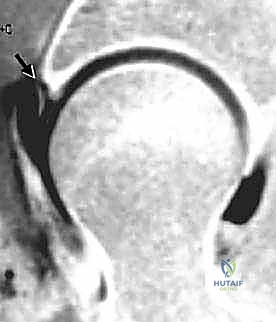

- الرنين المغناطيسي مع الصبغة المفصلية (MR Arthrogram): وهو المعيار الذهبي لتشخيص تمزقات الشفا الحقي وتلف الغضاريف. يتم حقن صبغة داخل المفصل قبل التصوير لإبراز أي تسرب للصبغة عبر التمزقات.

ثانياً: تمزق الشفا الحقي (Acetabular Labral Tears)

يمكن أن يتمزق الشفا الحقي نتيجة للاصطدام الفخذي الحقي المستمر، أو بسبب صدمة حادة (مثل حوادث السيارات أو الإصابات الرياضية)، أو الحركات المتكررة (مثل الجمباز والباليه)، أو حتى بسبب التآكل الطبيعي مع تقدم العمر. التمزق يؤدي إلى فقدان "الختم الهيدروليكي"، مما يقلل من تزييت المفصل ويزيد من الضغط على الغضاريف، مسرعاً من عملية الخشونة.